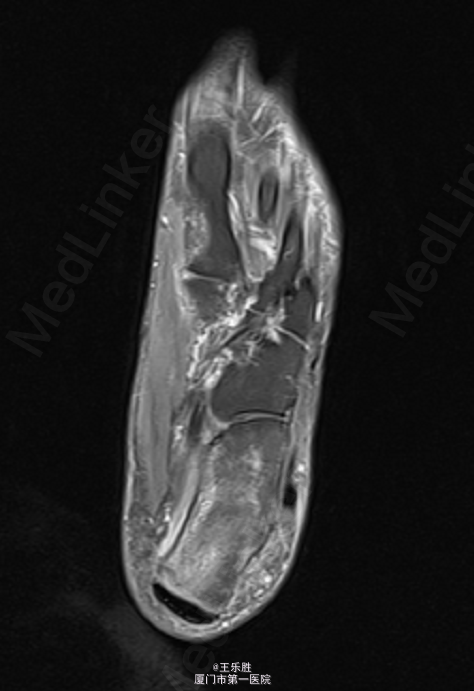

左足跟轻度肿胀,局部皮肤无红肿及皮温升高,轻压痛,左足背动脉搏动存在,肢端血运感觉正常,足趾活动尚可。MRI提示:“左足跟骨水肿”.

初步诊断:左足跟痛. 行CT(左下肢)检查提示:左跟骨骨折,断端稍嵌插、骨质增生样密度增高,跟骨结节骨质增生。余骨未见明显骨质异常,关节间隙如常.